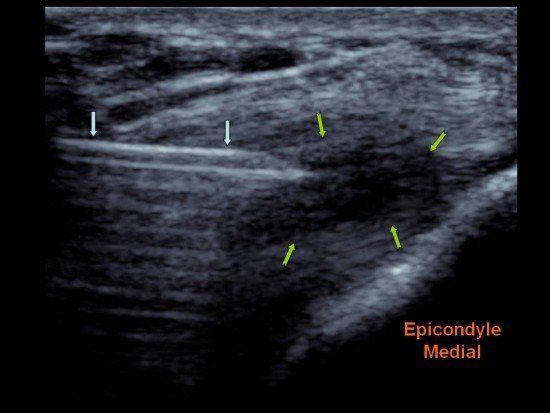

La membrane synoviale va être le siège d’une inflammation et produire trop de liquide synovial, ce qui va créer un gonflement de l’articulation, on parle d’ « épanchement de synovie ».

Ces plaquettes (responsable de la formation de caillots lors de la coagulation sanguine) libèrent, au contact de la lésion ostéocartilagineuse du genou, ou des lésions ligamentaires et tendineuses, une douzaine de puissantes protéines contenues dans les granules alpha des plaquettes, relâchées lors de l’activation des plaquettes, et responsables de la cicatrisation tissulaire.